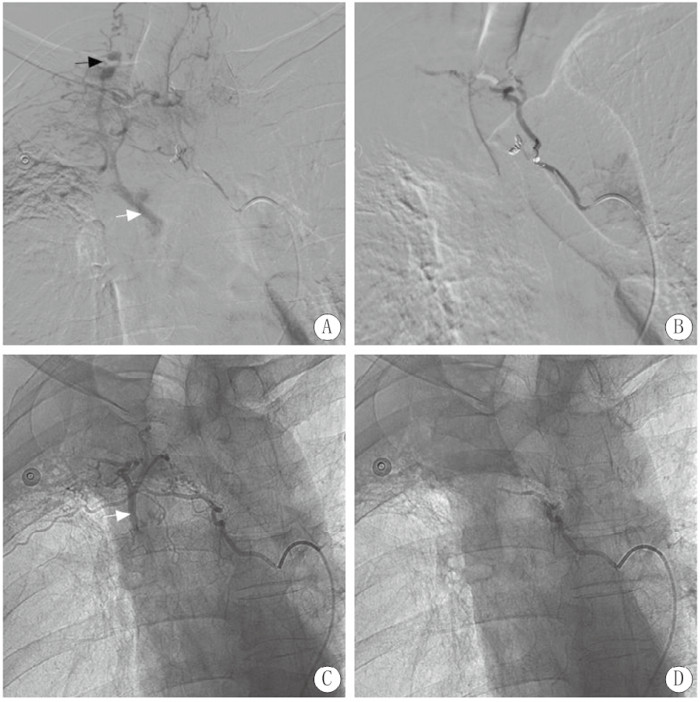

入院后每日咯血约500 mL,患者家属要求行介入栓塞止血,术中患者不间断咯血,数字减影血管造影(digital substraction antiography, DSA)示右第四肋间动脉增粗,远端可见肺静脉分支显影,右支气管动脉主干增粗与右第3肋间动脉共干,支气管动脉远端分支增多杂乱,肺组织富血管化,可见肺静脉分支显影。使用自制明胶海绵颗粒(直径约1 mm)进行栓塞止血,患者家属要求不用钢圈栓塞,栓塞后复查造影仅肋间动脉及支气管动脉主干保留,异常血管及静脉瘘消失(图 2)。栓塞后患者出血停止,术后4 d患者在排便和咳嗽后再次出现大量咯血,1 h总量超过200 mL,停用垂体后叶素半小时后再次进行介入栓塞止血治疗。术中DSA右支气管动脉主干再通,远端杂乱血管减少,支气管动脉-肺静脉瘘未显示,共干的第3肋间动脉出现假性动脉瘤(图 3黑箭头)和肋间动脉-肺静脉瘘(图 3白箭头),用泰尔茂2.7 F微导管超选后使用直径1 mm明胶海绵颗粒、COOK 2/3、2/4和2/5 mm微钢圈各一个进行栓塞后,复查造影示仅主干保留,术中还发现一支左右共干支气管动脉但与咯血无关(图 3)。术中造影还发现右第4肋间动脉再通,并通过侧支与第3肋间动脉吻合,可见假性动脉瘤显影(图 4黑箭头),肺静脉瘘(图 4白箭头)仍然存在,使用1 mm明胶海绵颗粒和COOK 2/3 mm微钢圈进行栓塞后只保留了主干;术中发现上次介入治疗时漏诊的一支血管-右第5肋间动脉,其主干增粗,远端异常血管增多,并可见肺静脉瘘形成(图 4白箭头),使用1 mm明胶海绵颗粒和COOK 2/4 mm微钢圈进行栓塞后,复查造影仅主干显影(图 4)。术后未出现并发症,术后3 d每日咳出暗红血约20 mL,之后未再出现咯血。随访3个月未见复发出血。

| 注:A为右第四肋间动脉再通,并通过侧枝与第三肋间动脉吻合可见假性动脉瘤显影(黑箭头),肺静脉瘘(白箭头)仍然存在;B为栓塞后造影显示仅右第四肋间动脉主干显影;C为上次介入治疗时漏诊的一支血管-右第五肋间动脉,其主干增粗,远端异常血管增多,并可见肺静脉瘘形成(白箭头);D为栓塞后仅右第五肋间动脉主干显影 图 4 咯血复发后第二次介入治疗DSA图 |